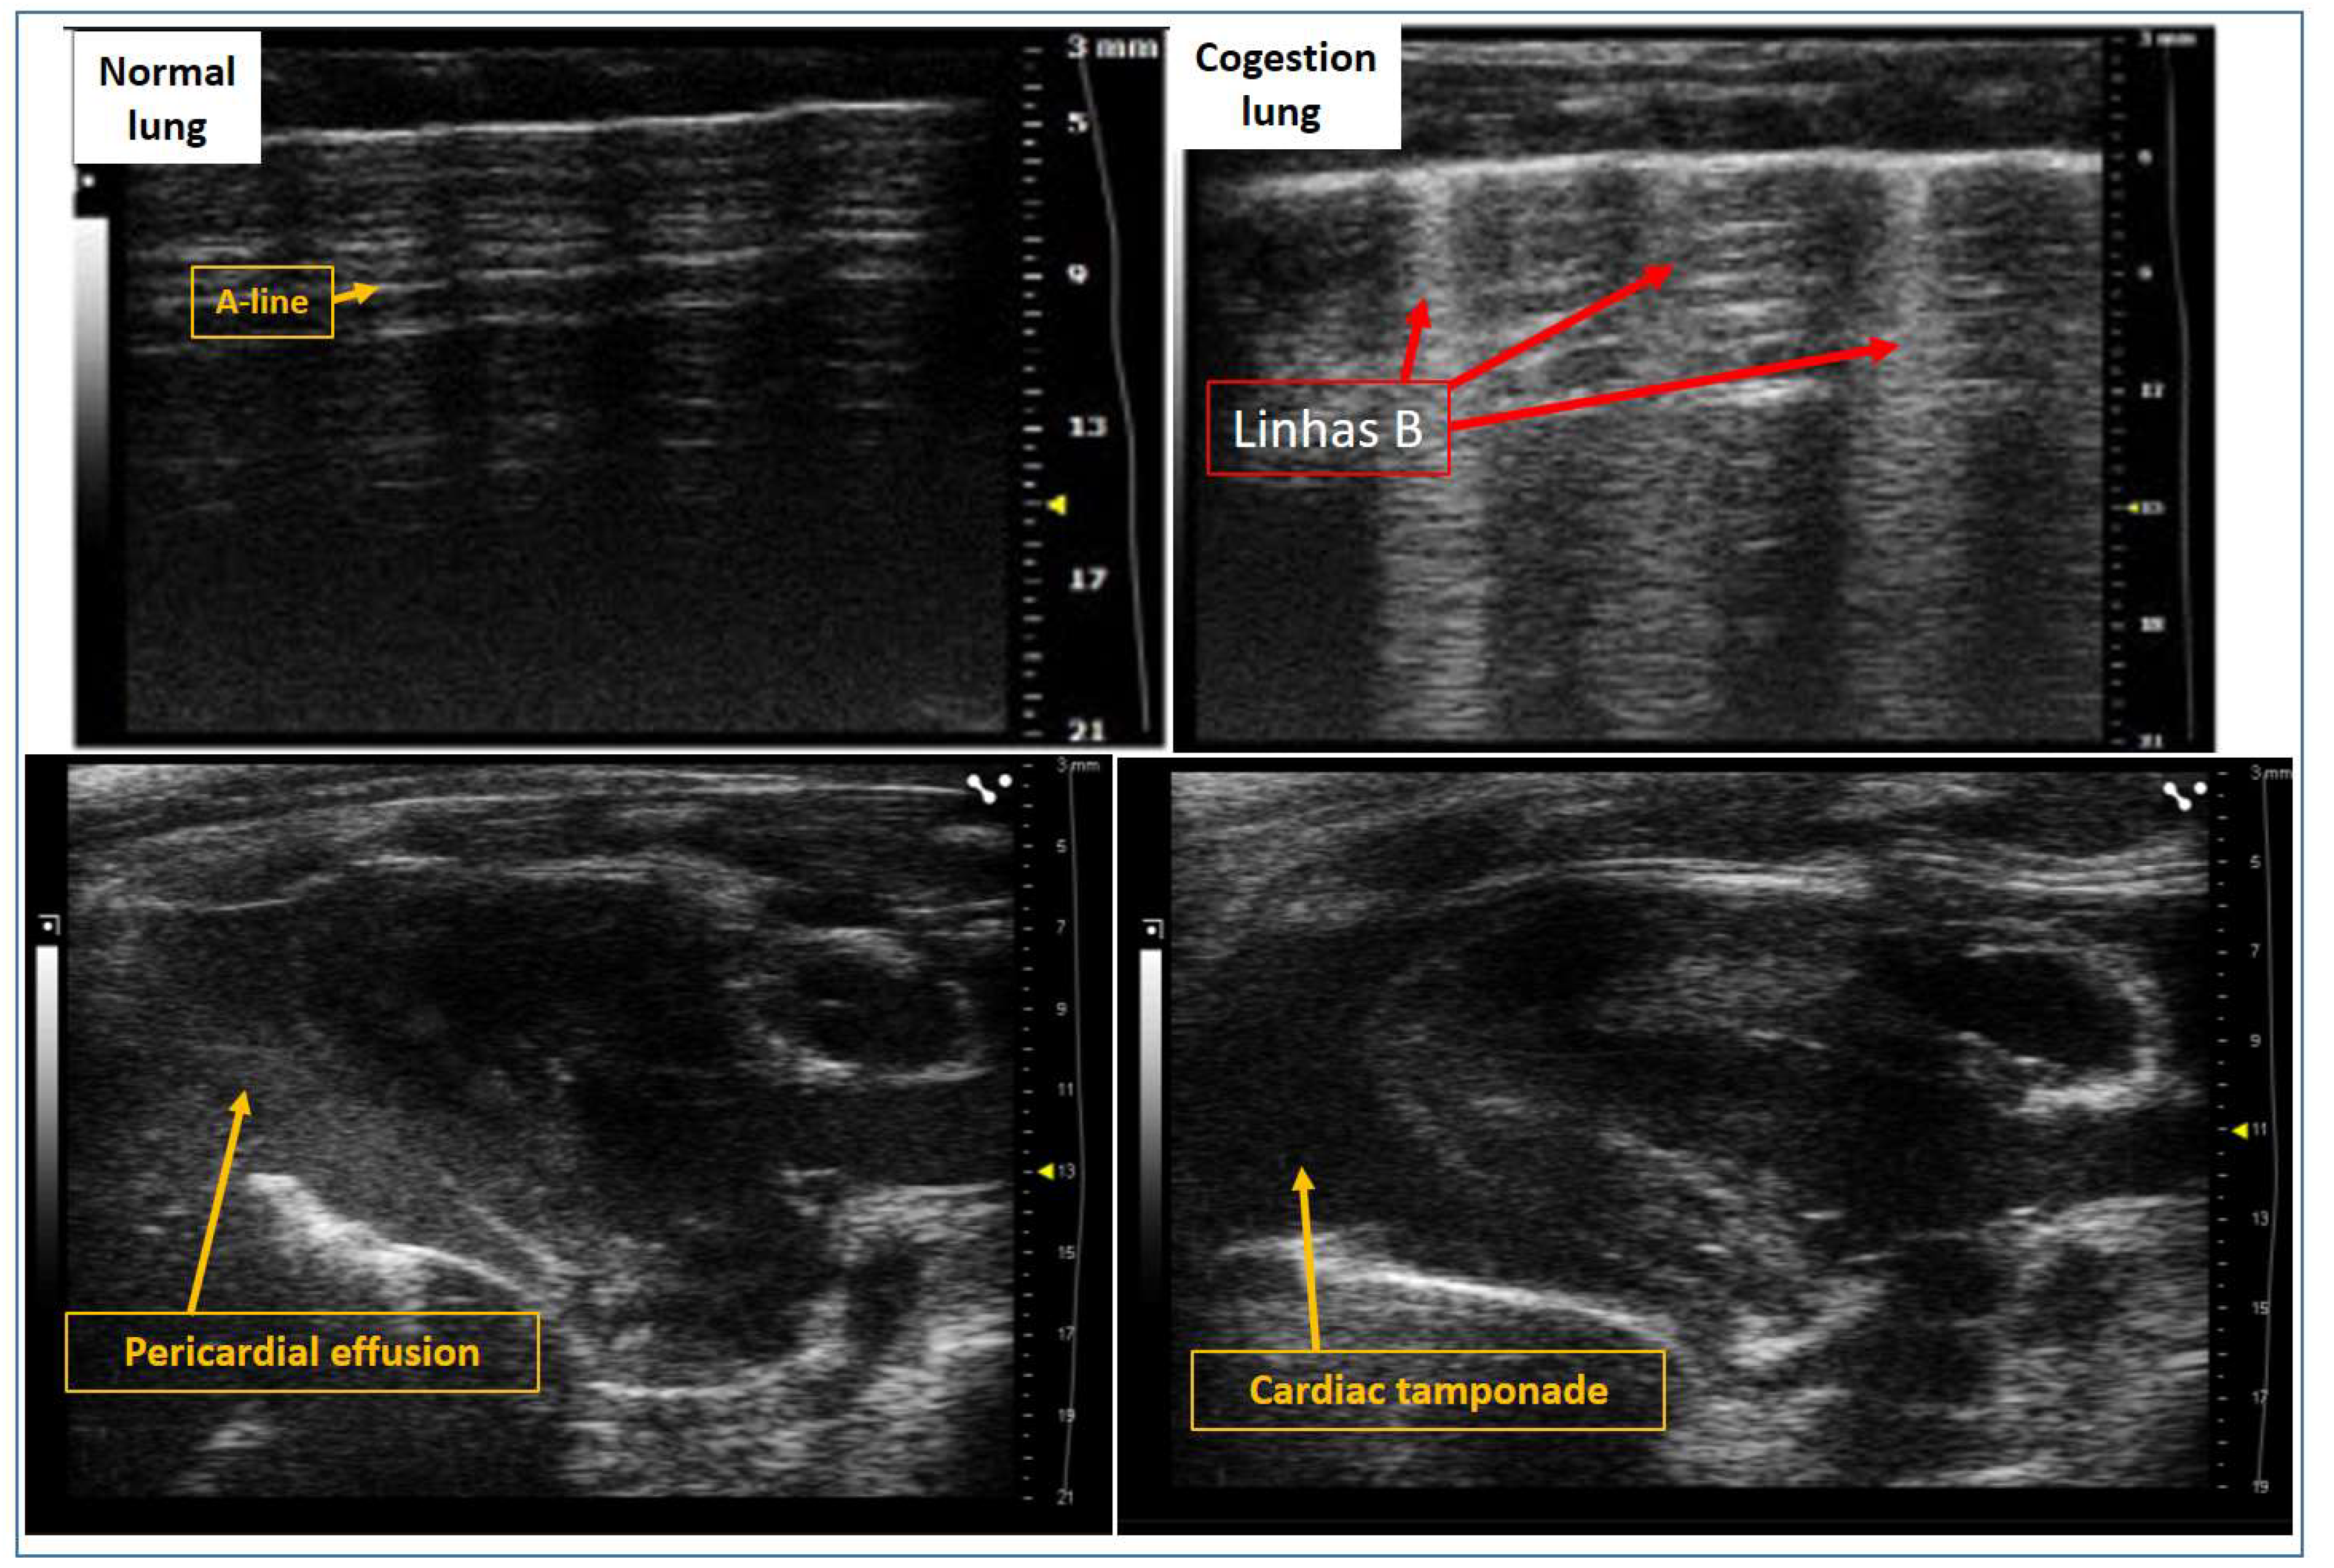

5. Evaluation of Pulmonary Congestion Using Lung Ultrasound in Rats